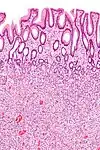

| Hyperplasique | Cryptes dentées non-ramifiées | Non | ![]() |

Hyperplasique polypose syndrome | |